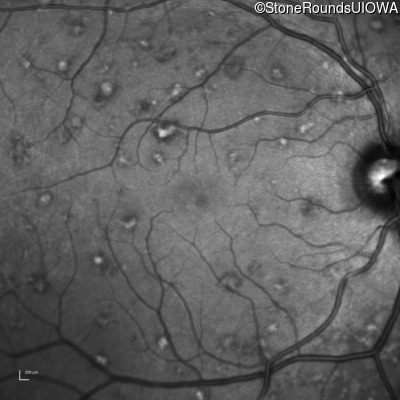

AR Stargardt Disease (IIA)

Age at visit: 30 years

This 30 year old asymptomatic man had fundus abnormalities identified incidentally on a routine exam.

Diagnosis & molecular findings

Disease Gene Allele 1 variant(s) Allele 2 variant(s) Inheritance mode

AR Stargardt Disease ABCA4 IVS30+1321 A>G Asn965Ser AAT>AGT AR